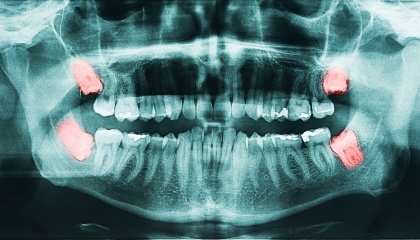

During your first visit, we will conduct a thorough review of your medical history and engage in a detailed discussion about the wisdom teeth removal process. We utilize X-rays to assess the position and condition of your wisdom teeth, enabling us to create a personalized treatment plan tailored to your specific needs and anatomical considerations. This plan will outline the associated costs, timeline, and steps involved in the procedure. We encourage you to ask any questions you may have; we are committed to addressing any concerns you might have and ensuring you feel fully informed throughout the process.